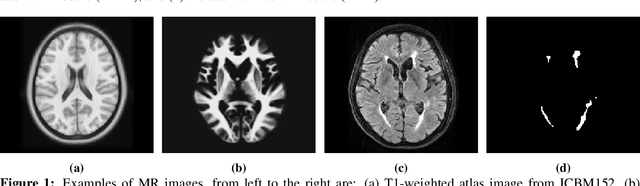

Abstract:White Matter Hyperintensities (WMH) are the most common manifestation of cerebral small vessel disease (cSVD) on the brain MRI. Accurate WMH segmentation algorithms are important to determine cSVD burden and its clinical consequences. Most of existing WMH segmentation algorithms require both fluid attenuated inversion recovery (FLAIR) images and T1-weighted images as inputs. However, T1-weighted images are typically not part of standard clinicalscans which are acquired for patients with acute stroke. In this paper, we propose a novel brain atlas guided attention U-Net (BAGAU-Net) that leverages only FLAIR images with a spatially-registered white matter (WM) brain atlas to yield competitive WMH segmentation performance. Specifically, we designed a dual-path segmentation model with two novel connecting mechanisms, namely multi-input attention module (MAM) and attention fusion module (AFM) to fuse the information from two paths for accurate results. Experiments on two publicly available datasets show the effectiveness of the proposed BAGAU-Net. With only FLAIR images and WM brain atlas, BAGAU-Net outperforms the state-of-the-art method with T1-weighted images, paving the way for effective development of WMH segmentation. Availability:https://github.com/Ericzhang1/BAGAU-Net